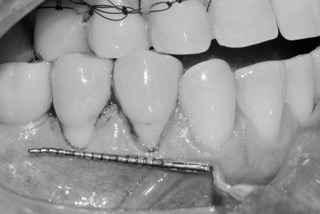

Proceso del tratamiento: